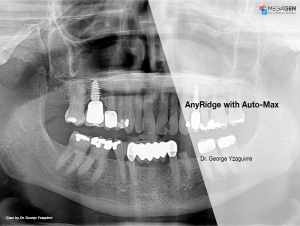

Aesthetic zone,AnyRidge,Clinical case,Dr. Achraf Souayah,Edentulous,Guided surgery,Immediate Placement,Mandibular Anterior,Mandibular Posterior,Maxillary Anterior,Maxillary Posterior,MEG-Rhein,MILA Kit,Overdenture system,Sinus Elevation